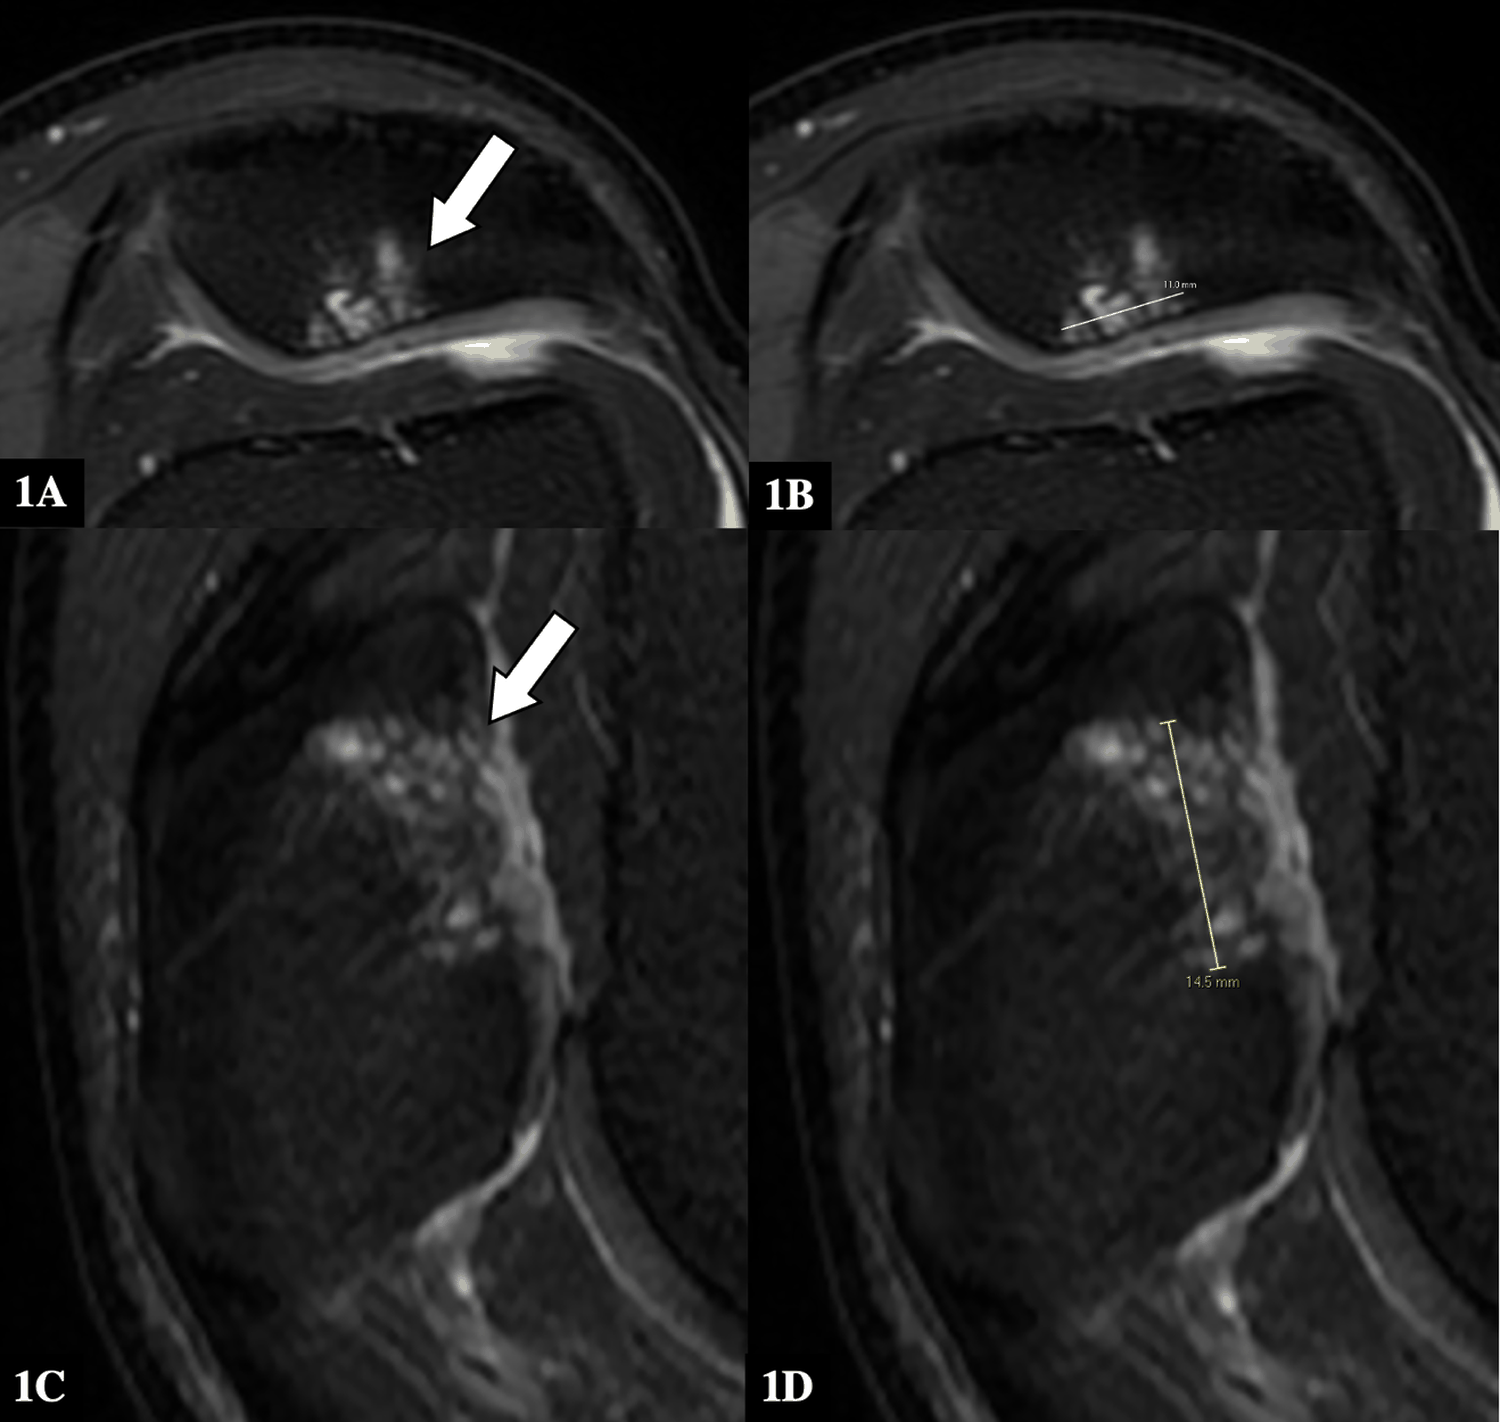

A 58-year-old male presented with left knee pain from a patella chondral defect at our tertiary institution and underwent a cartilage graft repair (HyaloFast; Anika Therapeutics, Italy). However, almost a year later, his left knee pain was noted to have recurred on follow-up. MRI cartilage studies showed features normally associated with graft viability, despite the patient’s persistent symptoms of knee pain on clinical examination.

He subsequently underwent a diagnostic arthroscopy, and the orthopedic surgeon noted that the surface of the previous cartilage graft was filled hyaline cartilage rather than fibrocartilage, and that there was no viable cartilaginous tissue at the site. The patient then had a revision cartilage patch repair surgery performed (ProChondrix CR; Stryker, USA). His left knee pain significantly improved after.

Notably, MRI cartilage T2RV mapping studies before and after the revision surgery were similar in appearance and showed features suggestive of graft viability, despite the clinical examination and history from the patient.